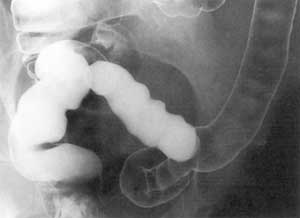

Неспецифический язвенный колит.

Рис. 2. Начальная стадия. Потеря тонуса и гаустрации кишки.